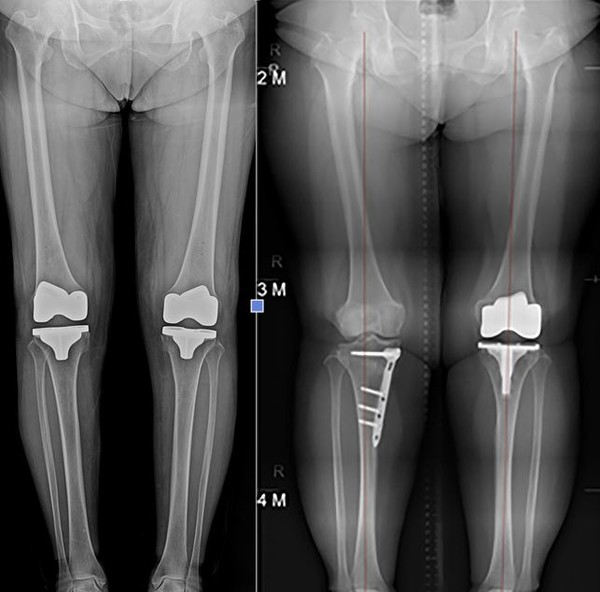

무릎 관절염은 비교적 젊은 환자의 경우에는 관절내시경 수술로 좋은 치료효과를 볼 수 있지만, 이미 관절 연골이 심하게 닳고 손상돼 있는 경우에는 인공관절 수술을 고려할 수밖에 없게 된다.

대표적인 치료법인 관절내시경 수술과 비교해보면 관절내시경 수술은 작은 구멍을 통해 내시경 카메라와 수술도구가 무릎의 연골에 접근해 찢어진 연골을 치료하고 염증을 씻어내지만 관절염이 오래도록 지속된 경우 인공관절 수술을 통해 무릎을 절개 하고, 상한 관절은 제거하고 인공관절로 교체를 하다 보니 내시경 수술과 비교 시 수술 후 통증도 더 있는 편이고, 회복기간도 더 길어지게 된다.

최근 로봇인공관절수술이 도입이 됐다. 인공관절 수술을 할때 뼈를 절삭(깍아내고)하고 인공관절을 집어넣게 되는데, 뼈를 깍아낼때 기존에는 사람이 했으나, 로봇인공관절 수술의 경우 로봇팔을 정형외과 전문의가 조작해 뼈를 깍아내게 된다. 기존의 사람이 직접 하던것에 비해, 로봇을 사용할경우, 뼈도 좀 더 보존할 수 있고, 피도 덜 나고, 통증도 적다. 따라서 재활운동도 조기에 시행하게 되며, 입원기간도 적고, 회복도 더 빠르다.

또, 흔히들 하는 걱정 중 “수술 전보다 움직임이 둔하고 뻗기도, 구부리기도 어정쩡해진다.”, “수술하면 수술 전 보다 걷기 힘들다.”는 등 우려섞인 주위의 조언이 많지만 경험이 풍부한 의사와 첨단로봇을 이용한 수술 후 조기 기능 회복과 퇴원 및 재활 기간 단축을 도와 환자가 빠르게 일상생활로 돌아갈 수 있게 해준다는 결론을 보여주게 됐다.